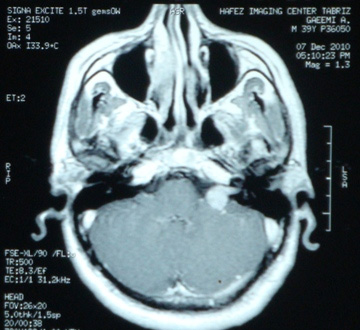

تومور در فضای بین مغز و گوش که زاویه پلی مخچه نامیده می شود، ایجاد می شود. آکوستیک نورما جزء تومورهای خوش خیم است اما خطر این تومور به دلیل رشد آن در فضای حساس و فشار آوردن آن به ساختارهای حیاتی مانند اعصاب جمجمه، مغز و ساقه مغز است. شایع ترین نشانه تومور شامل کاهش شنوائی در گوش مبتلا، وزوز گوش و عدم تعادل می باشد. برای به دست آوردن بهترین نتیجه، تشخیص صحیح به منظور انتخاب بهترین روش درمان در این مشکل است. برای تشخیص نورینوم آکوستیک ام آر آی توصیه می شود. این روش تصویر برداری نه تنها به تشخیص کمک می کند بلکه می کند وسعت و عوارض احتمالی مانند هیدروسفالی را مشخص می کند.

نمونه های زیر MRI پزشک متخصصی است که توسط اصغری جراحی شده اند: